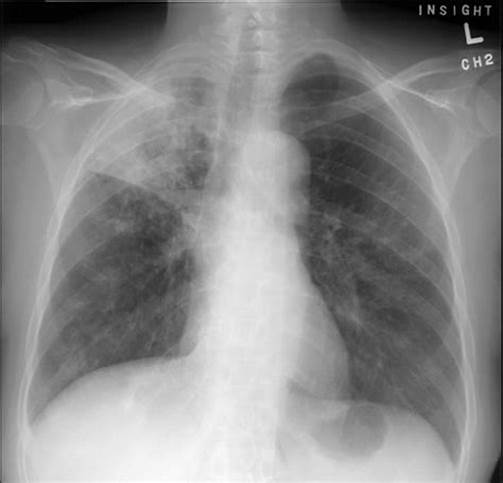

另外一个病例,男性,46岁,爱潜水,平时身体很棒,因发热、咳嗽就诊,肺部CT提示右上肺结核灶。

入院后,检查发现白细胞高,C反应蛋白高,痰多,呈黄色或灰色。

痰检阴性、T-SPOT阳性、PPD阴性。

医生的诊断是打了问号的肺结核和肺炎,正要抗结核治疗,患者也准备吃药。

不料,用抗菌药2~3天后,患者症状明显好转,正好是周末,就没有给开抗结核药。

一周后,为了稳妥起见,复查了一下肺部CT,发现所谓的“结核病灶”竟然明显吸收。

患者所用药是“头孢”,对结核分枝杆菌是没有效果的。

这位患者后来继续原方案治疗,病灶完全吸收了。